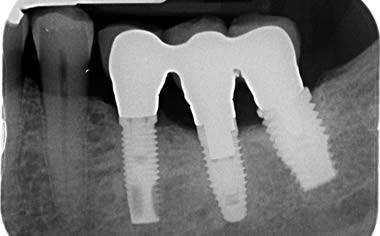

Back teeth replaced by dental implants

Case One (3 images)

Missing lower teeth replaced by three dental implants and crowns.